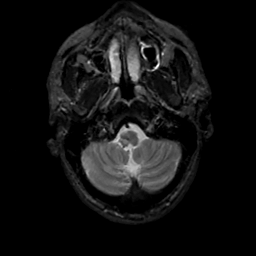

MR Study #12, May 12, 1991 -- Slice #6